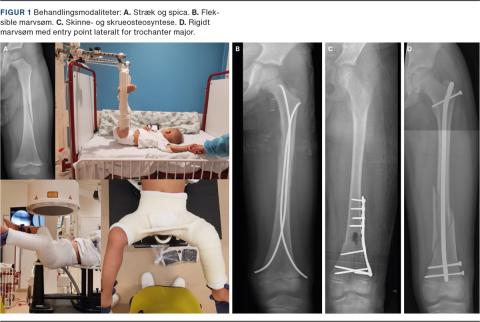

Behandlingsindikation for nonoperativ vs. operativ behandling og målsætning mhp. at genoprette benets længde, akse og rotation afhænger af barnets alder, vægt og frakturtype (Figur 1). Vejledende acceptable fejlstillinger for skaftfraktur fremgår af Tabel 1 [7].

Til de mindre børn benyttes vertikalt galgestræk (Bryants traktion), hvor begge ben ophænges med kontravægt, så barnets baller akkurat løftes fri af underlaget (Figur 1A). Når barnet hænger i strækket, kan der foretages røntgenkontrol, og forkortning samt rotationsfejlstilling kan helt eller delvist korrigeres. Longitudinelt stræk (Hamilton-Russell-traktion) giver mulighed for at færdigbehandle større børn, men dette setup forefindes kun få steder. Hudkomplikationer som sår og irritation er hyppige komplikation i forbindelse med plasterstræk (Figur 2A).

Alternativet til plasterstrækbehandling er anlæggelse af en hoftespica i generel anæstesi (Figur 1A). I Nordamerika har man i en del år med gode resultater behandlet femurfrakturer hos børn med hoftespica frem for strækbehandling [10, 11]. Anlæggelse af en hoftespica kræver specielt lejringsudstyr og kompetent personale, hvorfor behandlingen ofte kun foregår på et børneortopædisk center. Spicabehandling har traditionelt været foretaget efter få dage med strækbehandling i ønsket om at få genskabt længden på frakturen og opnå begyndende heling og stabilitet i frakturen. I nyere studier er det dokumenteret, at man i flere tilfælde kan anlægge spica tidligt (< 48 timer) og dermed reducere indlæggelsestiden [12, 13]. Det er også en praksis, som i stigende omfang benyttes i Danmark.

Ved operativ behandling af femurfrakturer hos børn med åbne vækstzoner benyttes der i dag overvejende den ovennævnte teknik med indsættelse af fleksible marvsøm (Figur 1B). Metoden er udviklet ved børnehospitalet i Nancy i Frankrig. Teknikken kræver oplæring i korrekt anvendelse. Mest almindeligt benyttes en retrograd teknik, hvor to fleksible marvsøm indsættes lateralt og medialt fra metafysen (Figur 1B). Ved at forbøje marvsømmene i c-form kan der opnås spredning af sømmene på niveau med frakturen, hvilket medfører trepunktsfiksation. På denne måde kan selv relativt ustabile frakturer stabiliseres [16, 17]. Teknikken kræver erfaring, og hvis man vælger en for lille sømdiameter, eller man ikke opnår tilstrækkelig trepunktsfiksation, er der risiko for frakturskred (Figur 2C). I en del tilfælde er det derudover nødvendigt at foretage åben reponering for at opnå korrekt længde, akse og rotation [18]. Gener i form af smerter og hudproblemer fra de isatte marvsøm forekommer jævnligt (Figur 2B) [19]. Intern fiksation af femurfrakturer hos børn giver dog samlet set et godt klinisk resultat, og børnene kan mobiliseres og hjemsendes hurtigt. Alternativet til fleksible marvsøm er en submuskulær skinne eller ekstern fiksation (Figur 1C).

Rigide låste marvsøm anvendes tiltagende hyppigt hos større børn og er vores foretrukne behandling, når marvkanalens diameter tillader det (Figur 1D, Figur 2C). En af årsagerne til dette er en stigende komplikationsrate ved anvendelse af fleksible marvsøm hos overvægtige mindre børn eller større børn [20]. Der er dog ingen fast grænse for, hvor store børn der kan behandles med fleksible marvsøm. Det nordamerikanske børneortopædiske selskab sætter den øvre grænse for at benytte fleksible marvsøm hos børn til 50 kg [15]. Desuden er der heller ikke konsensus om den nedre aldersgrænse for brugen af rigide låste marvsøm.

Ved behandling med låste marvsøm opnås der hurtigt smertefrihed og god rehabilitering [21]. Mange større børn har en marvkanal, der gør det muligt at benytte rigide, antegrade, låste marvsøm. Problemet har dog været at opnå sikker adgang til marvkanalen. Caput femoris har sin egen blodforsyning hos børn. Blodforsyningen udgår fra a. circumflexa femoris medialis [22]. Det er påvist, at entry point i fossa piriformis eller ved toppen af trochanter major påfører børn og unge en ikke ubetydelig risiko for avaskulær nekrose af caput femoris [23]. Der er udviklet nyere pædiatriske marvsøm til et entry point lateralt på trochanter major, hvilket er en mere sikker adgang til marvkanalen hos børn og unge [23]. Vækststandsning af trochanterapofysen er en teoretisk komplikation uden betydende effekt efter otteårsalderen [24].